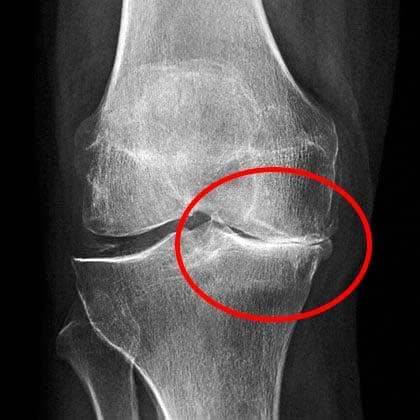

Imagen 3

Las radiografías mostraban un serio desgaste en las articulaciones.

Busqué la opinión de otro especialista y me dijo lo mismo: sin cirugía, pocas esperanzas de una recuperación total. Sin embargo, no disponía de ese dinero ni quería endeudarme, y tampoco había garantías de que todo saliera bien.